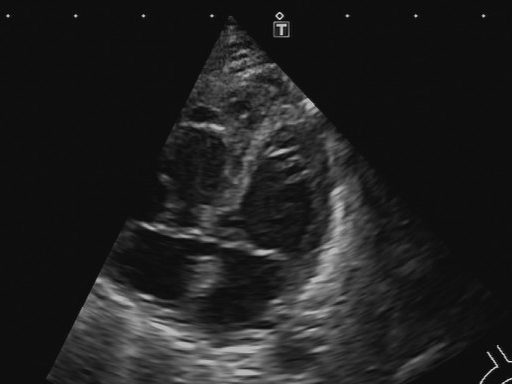

Ultraschall des Gehirns

Gerade nach einer schwierigen Geburt, beispielsweise bei einer Entbindung mit Saugglocke, empfehlen wir eine Ultraschalluntersuchung des Gehirns Ihres Neugeborenen.

Die Untersuchung erfolgt über die noch offene Fontanelle, ist völlig schmerzfrei und ermöglicht es, mögliche Auffälligkeiten frühzeitig zu erkennen.